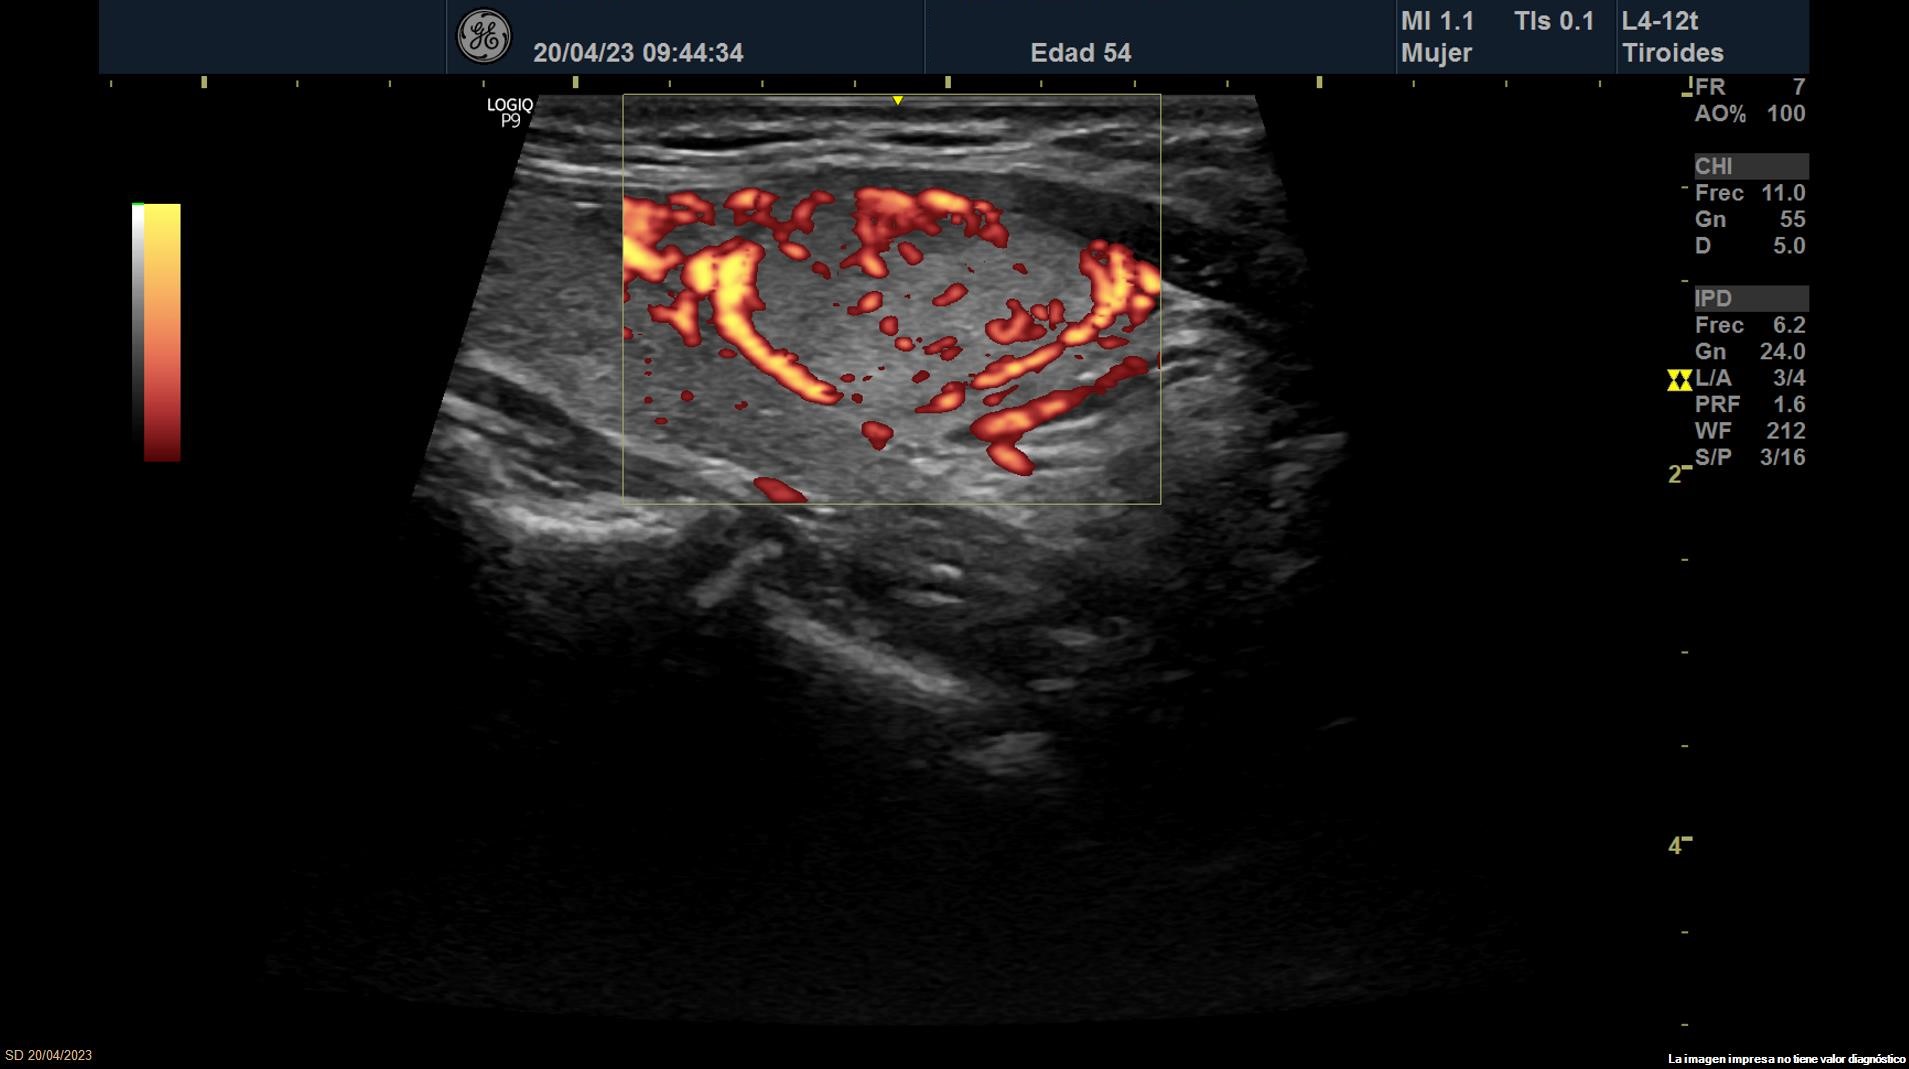

• Lóbulo tiroideo izquierdo: tamaño normal. En la mitad inferior se objetiva un nódulo de 11 x 14 x 20 mm (Vol 1,52 ml), bien definido, sólido e iso/hiperecoico, con halo fino hipoecoico, sin calcio y con vascularización de predominio periférico (ATA: baja sospecha).